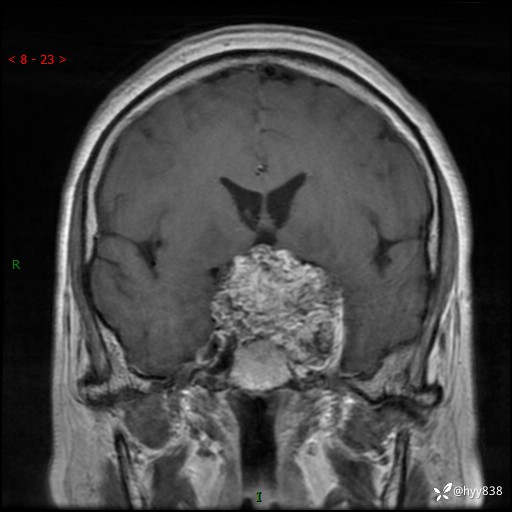

鞍区MRI平扫

T2WI

增强 COR +SAG